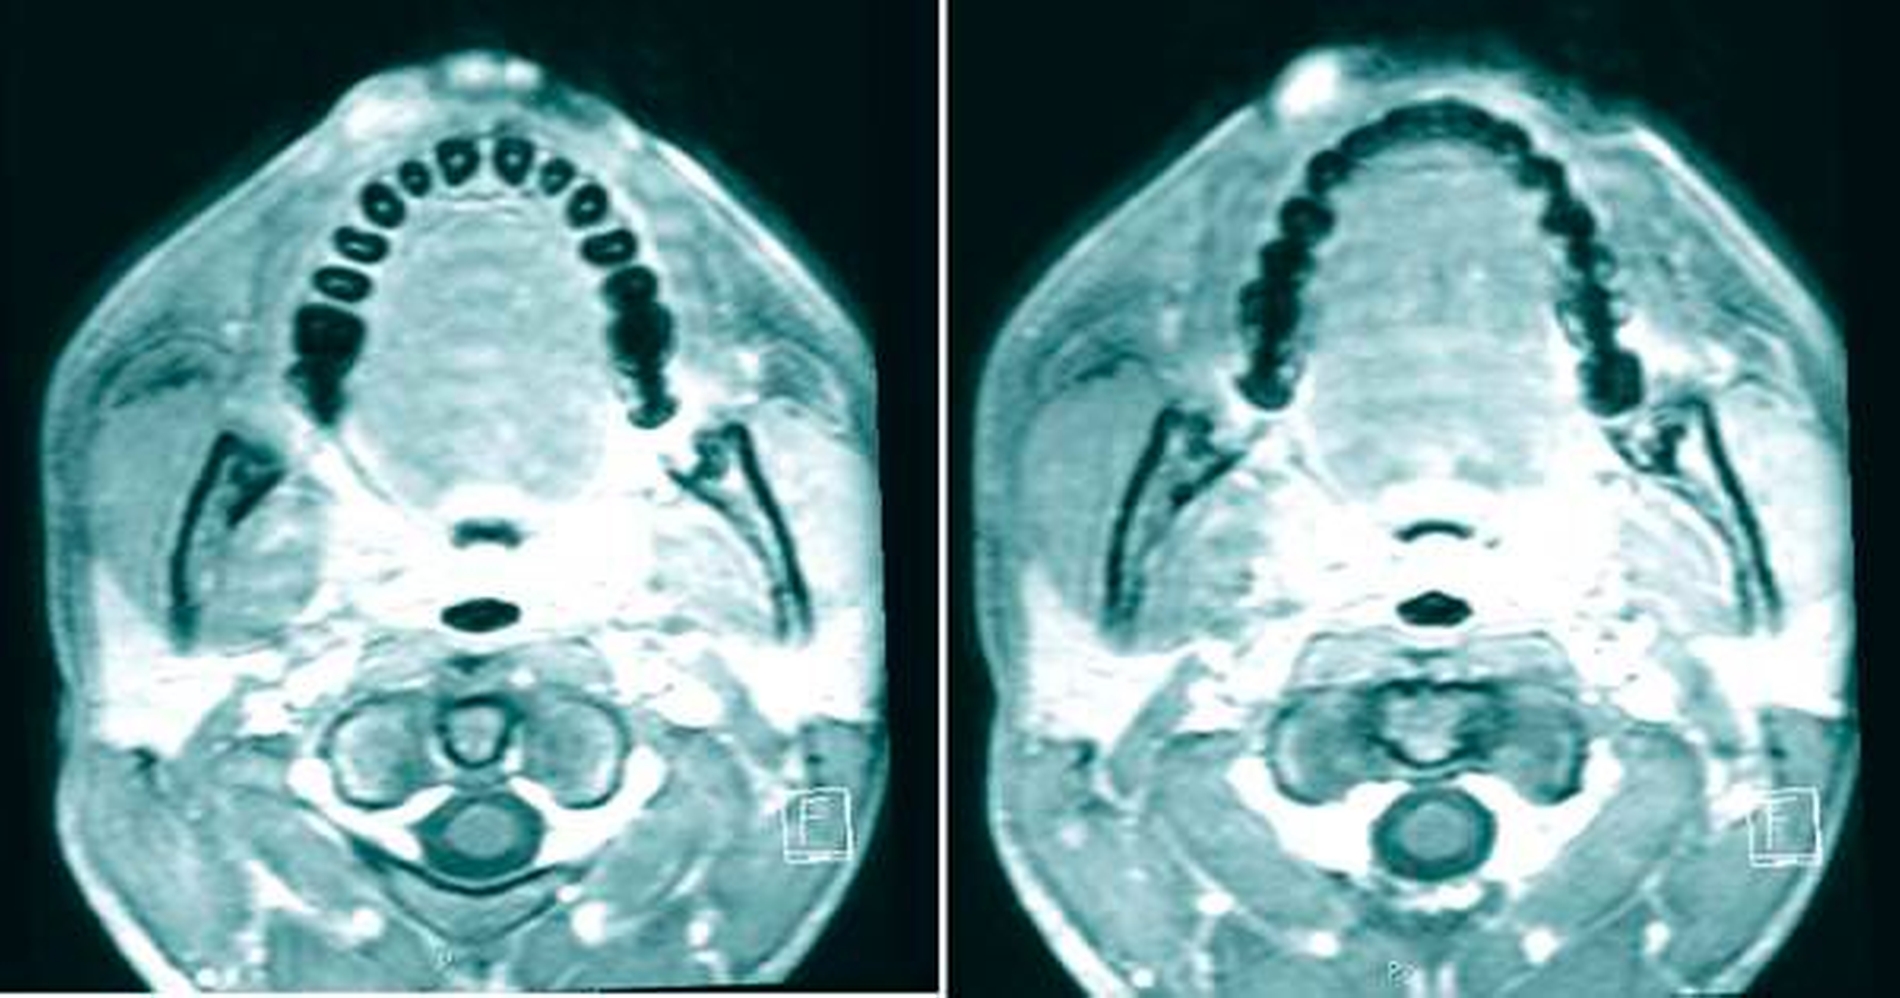

Bei dem ansonsten völlig gesunden Patienten erfolgte zur Bestätigung der Diagnose eines Hämangioms / einer vaskulären Malformation eine Magnetresonanztomografie (MRT) mit Kontrastmittel. Hier zeigten sich zwei Läsionen an der Oberlippe rechts paramedian, die multiple in der T2-Wichtung hyperintense und in der T1-Wichtung muskeliso- bis gering hypointense Anteile aufwiesen. Es konnte eine Gefäßversorgung via Gefäßäste aus der A. labialis superior nachgewiesen werden (Abbildung 2). Unter der radiologisch bestätigten Vermutung, dass es sich um eine angeborene Fehlbildung des peripheren Gefäßsystems handelte, erfolgte die operative Entfernung desselben in einer ambulanten Intubationsnarkose (Abbildungen 3 bis 5). Beide Befunde wurden in toto ohne Sicherheitsabstand exstirpiert, wobei sich der kraniale Tumor unter dem M. obricularis oris befand, der nach Durchtrennung und Entfernung des Tumors durch entsprechende Nähte rekonstruiert wurde.